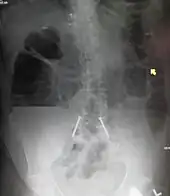

Upright abdominal X-ray demonstrating a small bowel obstruction. Note multiple air fluid levels.

Upright abdominal X-ray of a person with a large bowel obstruction showing multiple air fluid levels and dilated loops of bowel